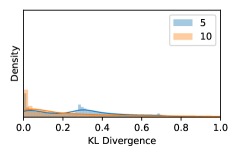

5.1 Distribution of Uncertainty Scores

Distribution of Uncertainty Scores Across Different Severity Levels As explained in Section 3, each uncertainty metric essentially defines an order/ranking among the data points. We conducted an analysis to better understand what data will be assigned high uncertainty under a particular uncertainty metric . Picking out the highest ranked data points (), we calculated the ratio of data points from each SL. Figure 4 summarizes the results as box plots for the Kaggle-DR and the Messidor-2 datasets; additional detailed statistics can be found in Table S.1 in the supplementary materials. From the plot and table, SL1 & SL2 examples account for a higher proportion among the top-ranked uncertain examples across the three ensemble methods. This finding matches our intuition that incipient disease examples (SL1 & SL2) are more likely to be considered uncertain by ensemble methods due to their ambiguity.

Uncertainty Scores on Out-of-Distribution Datasets As an additional experiment, we also tested the performance of the ensemble models on o.o.d. data inputs, which is a classic application of prediction uncertainties [1]. For this task, we produced distribution plots similar to those in Figure 4 for the previous experiment in our supplementary materials. The visualizations for the two o.o.d. image datasets can be found in Figure S.5 for ImageNet and in Figure S.6 for CIFAR-10. The results showed that the majority of o.o.d. data received higher uncertainty scores than in-distribution data for all three ensemble methods, suggesting that these ensemble methods would indeed perform well on o.o.d. detection tasks.

As discussed in Section 5.1 and Section 5.3 in the main paper, the mean metric and the stacking ensemble will have better performance in the precision (specificity) on the ambiguous data. Here, more detailed results are shown in Figures S.3 & S.6 and Table S.1. Figures S.3 & S.4 show the histograms of the uncertainty score for Kaggle-DR and Messidor-2 datasets that are the in-distribution (i.d.) dataset in our experiment and FigureS.5 & S.6 show the histograms for ImageNet and CIFAR-10 datasets, which is the o.o.d. datasets in our experiment. Each group of histograms contains results from the three evaluated ensemble methods (stacking ensemble, MC-dropout and TTA) and the three uncertainty metrics (mean, var and kl). Additional detailed results not displayed in Figure 4 can be found in Table S.1, which shows the proportion of the data of different SLs varies across different . For comparison, we also included in Table S.1 the results from single learners, and the proportions of data of different SLs (before any selection was made).